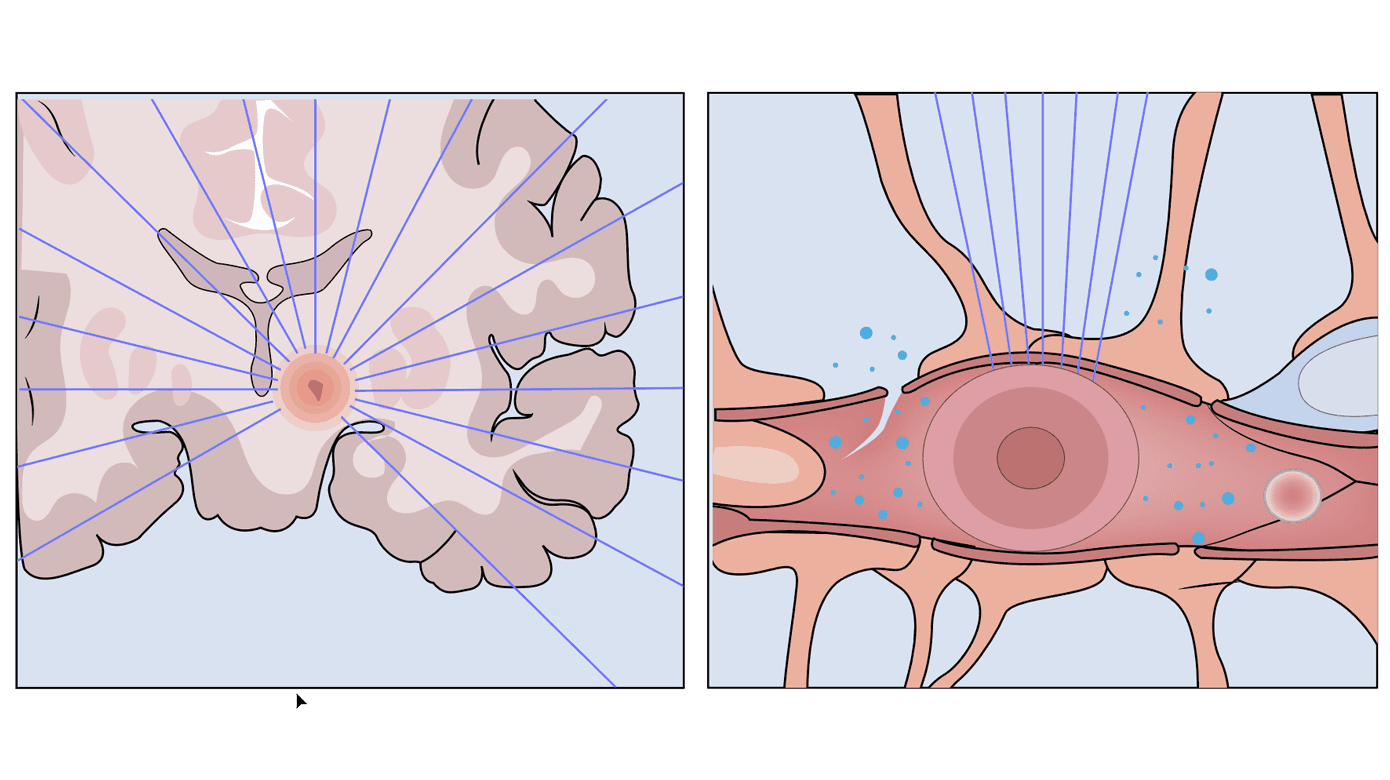

Der er udviklet en lang række eksperimentelle teknikker til FUS (Figur 2).

Termoablation

MRgFUS er aktuelt CE-mærket til behandling af essentiel tremor, tremordominant Parkinsons sygdom samt kroniske smerter. Termoablation af hjernevæv har været forsøgt hos primær hjernetumor-patienter i flere kliniske forsøg, men det samlede antal af patienter, der har modtaget behandling af denne type, er fortsat ganske begrænset [15]. Initialt var det teknisk nødvendigt at foretage en kraniektomi og implantere en transducer for at forhindre distortion af UL-bølgerne, men teknikken er blevet udviklet, så den kan anvendes noninvasivt [16]. Proceduren ved MRgFUS ved benigne og maligne tilstande er den samme og beror på høj-intens FUS. Det er et håb, at MRgFUS på sigt kan blive et ekstra behandlingstilbud til patienter med hjernetumorer, hvor der tidligere er givet maksimal strålebehandling, og hvor der i øvrigt ikke er mulighed for kirurgi.

Begrænsninger i teknologien bag FUS gør fortsat, at de ønskede læsioner skal befinde sig relativt centralt i hjernen, da passagen gennem kranieknoglen således er kortest, med minimal opvarmning af knoglevævet som komplikation [17].

Derudover er størrelsen af det område, det er muligt at behandle, fortsat ganske begrænset – dette er en udfordring, idet hjernetumorers diffuse vækstmønster gør, at det nødvendige behandlingsområde ofte er stort.

Åbning af blod-hjerne-barrieren

En af de mere velundersøgte teknikker ved FUS omhandler åbning af BBB (BBBO) [18]. Den kontrollerede, reversible og sikre åbning af BBB beror på en kombination af lav-intens MRgFUS kombineret med injektion af såkaldte mikrobobler (f.eks. UL-kontrastmidler), der gør, at UL-effekten fokuseres på kapillærniveau. Den præcise virkningsmekanisme er ukendt, men menes at tage udgangspunkt i »stabil kavitation«, hvor mikroboblerne oscillerer fra minimal til maksimalt stabilt volumen, hvorved karvæggen og dermed BBB udsættes for forskydningsspænding. På denne måde brydes tight junctions mellem endotelcellerne, og der skabes en forbigående spatiel afgrænset BBBO [19]. Ved højere frekvenser risikeres det, at boblerne brister – den afsatte kraft i karvæggen bliver derved så stor, at selve karvæggen og ikke kun BBB beskadiges. Teknikken minder om en operasanger, der kan ramme den præcise tone og derved få et vinglas til at vibrere og sidenhen ødelægges.

Integriteten af BBB har vist sig at genetableres inden for 6-24 timer. Der er dermed tid til, at de ønskede kemoterapeutika kan nå at passere BBB. Med FUS BBBO har man været i stand til at få dekstranmolekyler (2.000 kDa) til at passere BBB [20], ligesom det har været muligt at skabe transport af forskellige kemoterapeutika, virale vektorer og stam- og immunceller [21]. Selve åbningen af BBB kan valideres med MR med kontrast (Figur 3).

Temperaturstigningen i vævet ved teknikken er minimal, og effekten, der skal bruges ved BBBO, er under tre gange mindre end ved termoablation af hjernevæv [23].

Hypertermisk terapi, hvor temperaturen af vævet øges med højintensitets-MRgFUS til 40-45 ˚C, øger immunogeniciteten, radioterapi- og kemoterapifølsomheden. Teknikken er primært undersøgt til systemisk kræftsygdom, men i et enkelt ældre studie har teknikken været forsøgt anvendt mhp. behandling af GBM [28].

Sonodynamisk terapi, hvor UL-følsomme molekyler, der ophobes i tumorvæv (f.eks. 5-aminolevulinsyre) og vha. en endnu ukendt virkningsmekanisme »aktiveres« med FUS. Derved skabes frie reaktive radikaler, som ultimativt fører til apoptose af tumorcellerne [29].

Histotripsi, som beskriver høj-energi FUS, der afgives i mikrosekundpulse og fraktionerer væv mhp. ikketermoafhængig ablation af tumorvæv eller destruktion af tromber. Teknikken er kendt i urologien, hvor litotripsi er en lignende UL-teknik til transkorporal fjernelse af sten i urinvejene. Teknikken er fortsat eksperimentel [30].